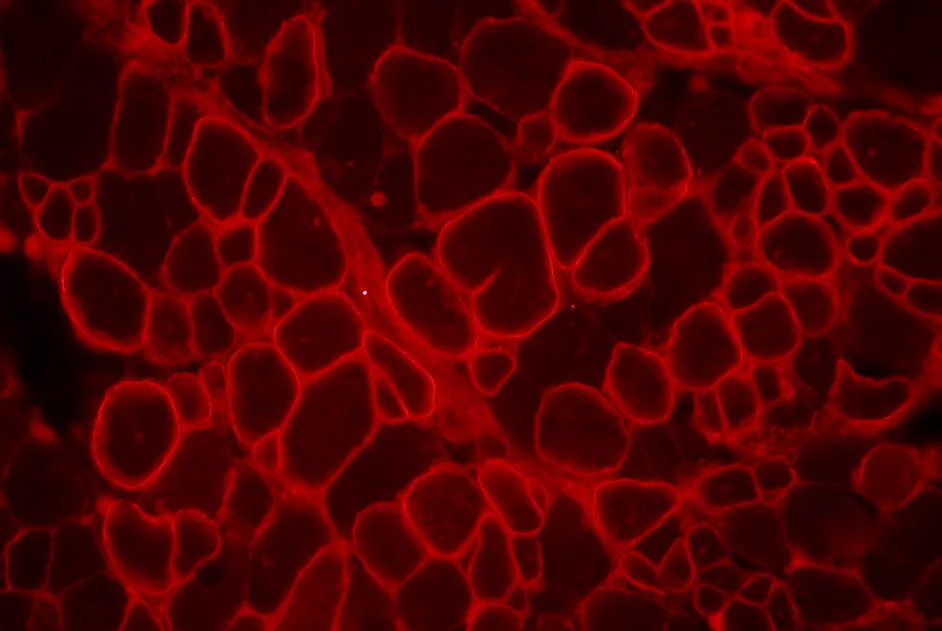

SMA liée à SMN1 et oligonucléotide antisens à un stade précoce

L’injection d’un oligonucléotide antisens dans le cerveau est plus efficace lorsqu'elle estréalisée à un stade précoce du développement dans la souris modèle de SMA.